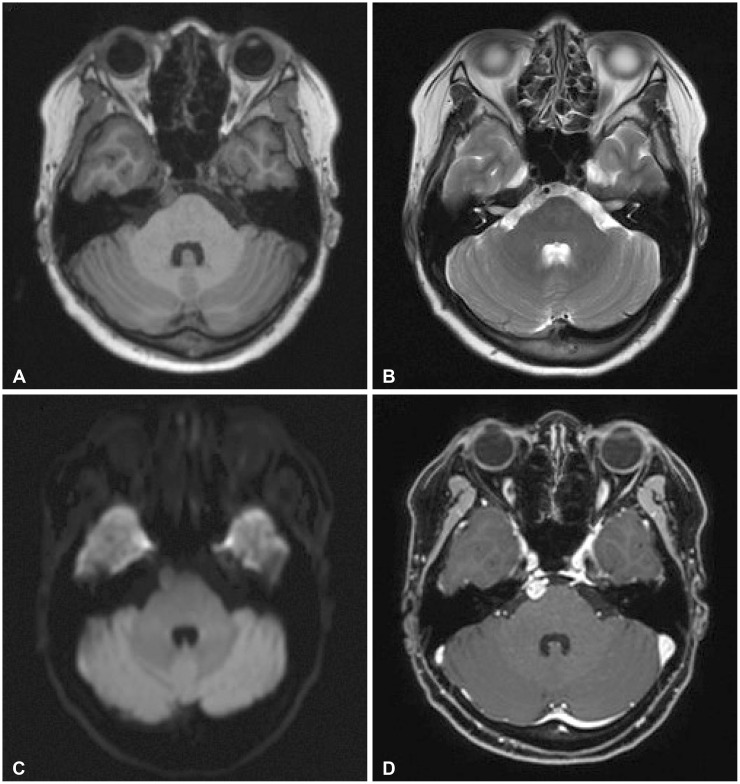

This case introduces the differential diagnosis of a well-enhancing lesion in the prepontine cistern of a 55-year-old female patient who was diagnosed with recurrent metastatic breast cancer. The patient was diagnosed with breast cancer 11 years ago and underwent a mastectomy and subsequent adjuvant therapy. Tamoxifen had been given for 5 years, and the treatment was completed. Five years after, she found a lung nodule on her routine chest X-ray examination. Based on her past medical history, systemic cancer work-up was done and it revealed multiple lesions in T10 vertebra, lungs, and mediastinal lymph nodes. Trans-bronchial needle aspiration was performed and the biopsy was a metastatic breast cancer. Brain MRI was taken as she was complaining of headache and it showed a well-defined, ovoid enhancing 0.9-cm nodule in the right prepontine cistern. Neuro-oncology tumor board evaluated the lesion as more likely to be an asymptomatic neurogenic tumor rather than metastasis based on radiological features including brainstem surfaced location, slightly high signal intensity on T2-weighted image and no diffusion restriction. To rule out leptomeningeal metastasis, a serial cerebrospinal fluid cytology examination (×3) was done and negative for malignant cells. Follow-up brain MRIs of 2 and 9 months showed no significant changes in the pre-pontine enhancing lesion.